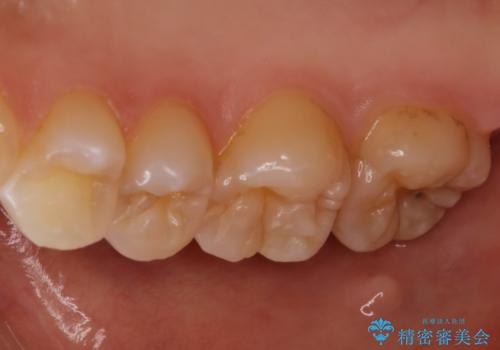

- 他院にて虫歯を指摘され、セカンドオピニオンを希望し当院へ来院されました。以前より磨きずらさと舌感の悪さは自覚していたそうです。清掃性、機能性に優れたセラミックインレーにて治療をすることとなりました。

レントゲンから昔詰めた保険の詰め物が入っていることが確認できました。詰め物と歯の隙間が虫歯になっていたためしっかり取り除き、適合の良いセラミックインレーを入れました。